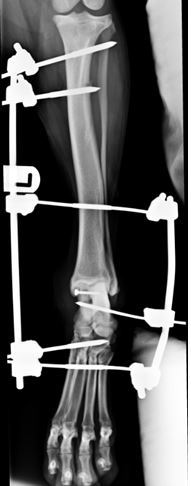

Post-operative radiograph showing lag screw repair being protected by a trans-articular fixator

Figure 3